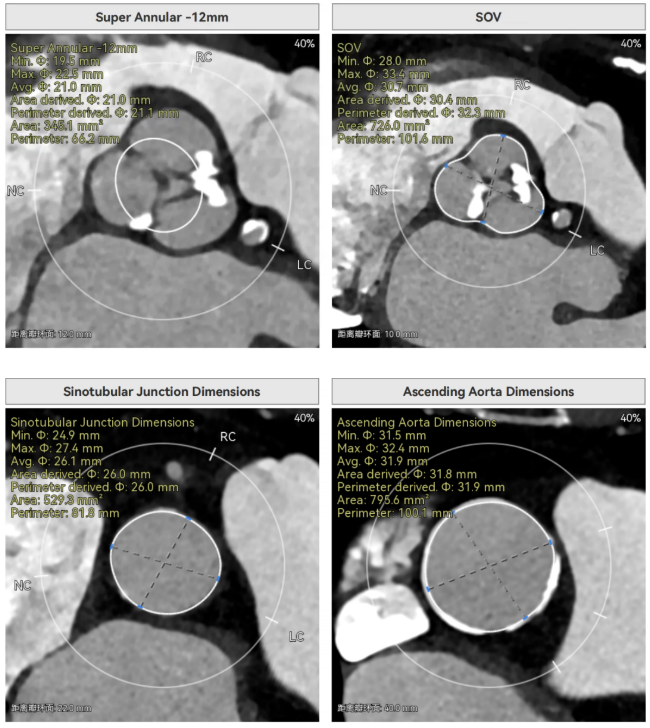

主动脉瓣环周长径21.9mm,小瓣环,LVOT直筒型结构;三叶瓣,左右融合(功能型二叶瓣),瓣叶轻微增厚并重度钙化,钙化主要分布在无冠窦瓣叶边缘及左右交界融合处,瓣上限制较重。

窦部空间适中,STJ内径偏小,升主动脉内径可。

双侧冠脉开口高度可,VTC空间充足,无冠脉风险,双冠内多处钙化,术中评估冠脉支架植入必要性。